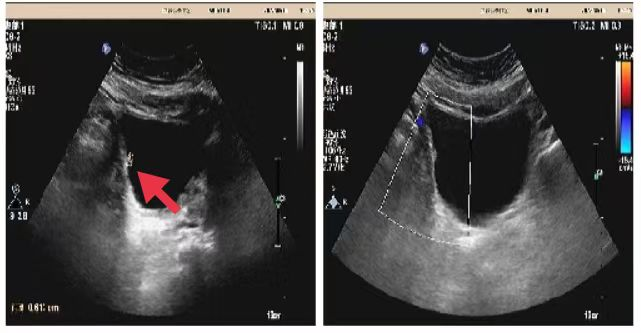

04、**男士,29岁

于2023年8月15日在宜昌仁康体检部体检,实验室及腹部彩超检查提示:AFP:130.11(已复查)ALT:155.1;AST:139.2;r-GT:621.5;彩超检查:肝内低回声1.9*1.5cm;肝实质回声不均。通知客户家属建议进一步检查。2023年9月5日跟踪回访,已在武汉某三甲医院进一步检查,确诊肝内胆管细胞癌,现治疗中。